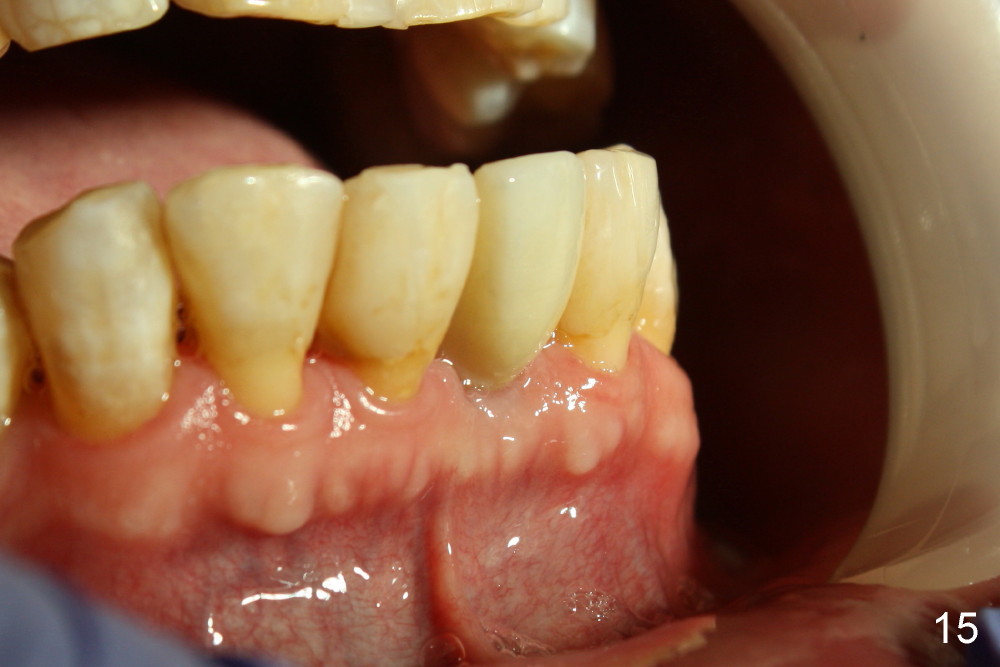

Fig.10,11 show 7 day follow up.  The permanent crown is seated 4.5 months postop (Fig.12).  Minimal bone resorption occurs at the crest 4 months postop (Fig.13), which is most likely associated with conservative approach (flapless).  The patient returns for follow up 2.5 months post cementation (Fig.14,15).  The implant remains in the bone 4 years post cementation (Fig.16 CT coronal section; lingual thread exposure, corresponding to preop defect in Fig.1).   There is mild coronal bone resorption 5 years 4 months post cementation (Fig.17).